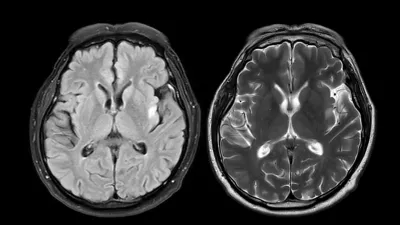

MRI brain scan axial T1W for detect Brain diseases sush as stroke disease, Brain tumors and Infections.